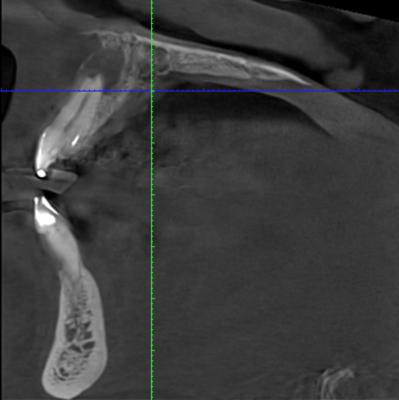

Case I got yesterday. Patient really wants an implant at #18 site. Fun case! ~60yo female, non-smoker, no DM, no osteoporosis or any other bone-related diseases.